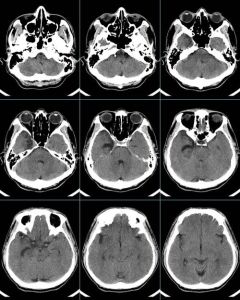

影像學檢查

腦部CT或MRI一般無異常。